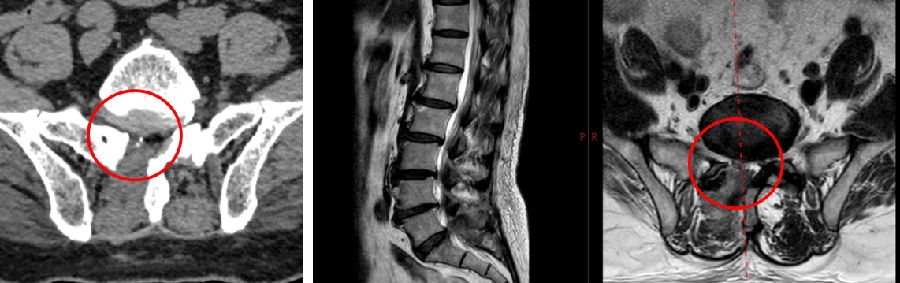

七、术后椎间盘囊肿

病例

男,31岁。

主诉:腰痛伴右下肢疼痛5月,加重2月。

查体:疼痛放射至右侧臀部、大腿外侧、小腿外侧。

九、类脊髓高压综合征

女,51岁。

主诉:腰疼伴左下肢疼痛麻木4个月。

既往史:椎间孔镜下椎间盘切除术(L4-5)。

术前

术中:术中硬膜破裂,灌洗液压力30mmHg,硬膜破裂后1小时出现血压升高,心率加快,手术持续2小时。

术后:延迟苏醒,拔管困难,转ICU,6小时候拔管神志恢复正常。

术后